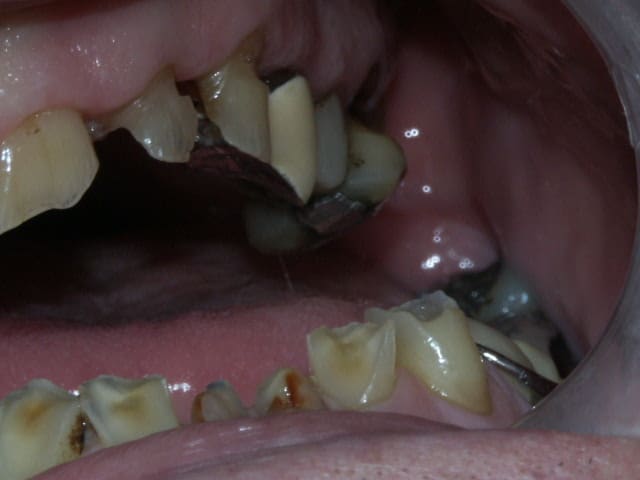

la suite...

on a eu des extractions non compensées à la mandibule qui ont provoquées des égressions des dents maxillaires postérieures.

une abrasion +++ du bloc antérieure avec égression "physiologique" au fur et à mesure de l'usure.

On a ainsi un décalage important (comme une marche d'escalier) de la courbe d'occlusion (Spee) entre le secteur antérieur et postérieur.

La difficulté de la thérapeutique consistera à rattraper le mieux possible ce décalage pour avoir une courbe d'occlusion "harmonieuse".

Il conviendrait d'augmenter la DV partout mais on risque de se retrouver avec les difficultés suivantes:

- en postérieur, l'augmentation de DV sera importante et on risque de vite se retrouver avec des couronnes avec un rapport couronne / racine défavorable.

Après il faut raisonner par sextant et ne pas hésiter à faire le ménage dans les secteurs trop compromis: 14 à 18 me paraissent bonne pour le cimetière des dents, de l'autre côté c'est à confirmer par des rétros mais ça n'a pas l'air beaucoup plus glorieux; en bas les secteurs postérieurs ne sont pas terribles non plus si tu considères que la première molaire secteur 3 n'est pas conservable, tu peux abandonner la deuxième aussi; secteur 4 ta molaire pourrait te servir d'appui pour une éventuelle PAP.

Pour la DV, une fois que toutes les dents égressées ont été retirées, je ne pense pas que tu auras de problème de place particulier, à confirmer avec les modèles (il faut juste compenser la perte de substance des molaires mandibulaires).